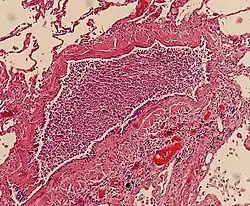

On gross pathology there are typically multiple foci of consolidation present in the basal lobes of the human lung, often bilateral. These lesions are 2–4 cm in diameter, grey-yellow, dry, often centered on a bronchiole, poorly delimited, and with the tendency to confluence, especially in children.

Light microscopy typically shows neutrophils in bronchi, bronchioles and adjacent alveolar spaces.[2]